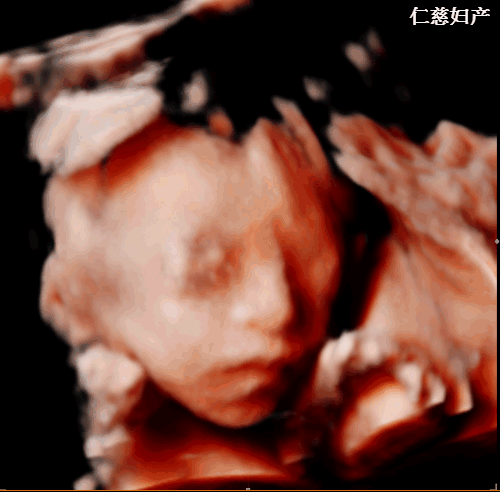

(仁慈妇产四维彩超实拍图)

四维彩超的全称是四维彩色超声诊断仪,能够多方位、多角度地观察宫内胎儿的生长发育情况,为早期诊断胎儿先天性体表畸形和先天性心脏疾病提供准确的科学依据。